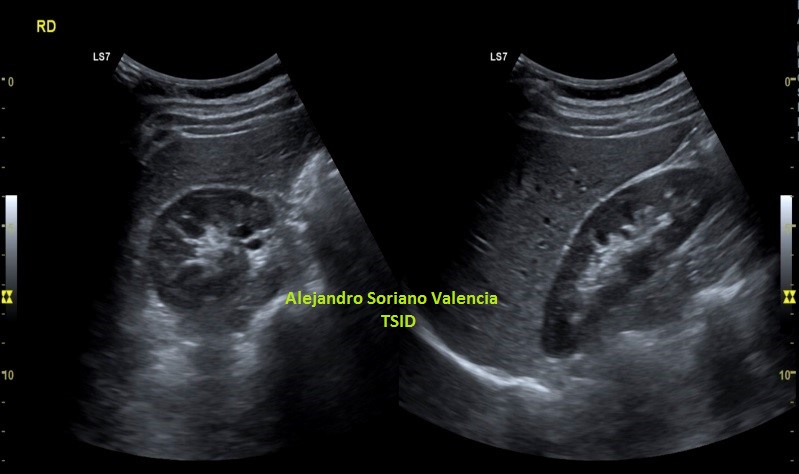

En este estudio, el estudio (perdón por la redundancia) contralateral no afectado es muy importante, diría yo, que una vez hecho el primer contacto con la lesión, lo primero es ir a comprobar la semiología del músculo y su ecoarquitectura normal. Encontramos en la zona contralateral sana un músculo de aspecto en “cielo estrellado”(punteado sobre fondo hiperecogénico) en el corte transverso y en forma de “penacho”(fibras alargadas hiperecogénicas sobre el fondo hipoecogénico de músculo) en longitudinal.

La imagen final demuestra una visión panorámica de los rectos abdominales inferiores demostrando los hallazgos que te he ido explicando durante el post. En este caso me hizo falta utilizar una función del ecógrafo muy útil que es la “función dual”, donde he dividido a pantalla en dos y he podido comparar en una misma imagen tanto a normalidad como la zona patológica, con un considerable aumento de la resolución de la imagen y un aumento en la calidad global de esta tanto en corte transverso como en longitudinal. Esta función dual permite el estudio comparativo con doppler. Muy útil, aunque el almacenamiento masivo de imagen en el pacs hace que esta función haya caído paulatinamente en desuso.